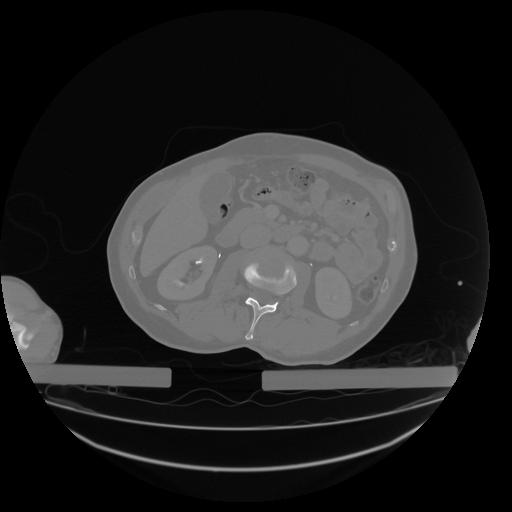

34 CUERPO,CE,Vol,1.0,CUERPO,,